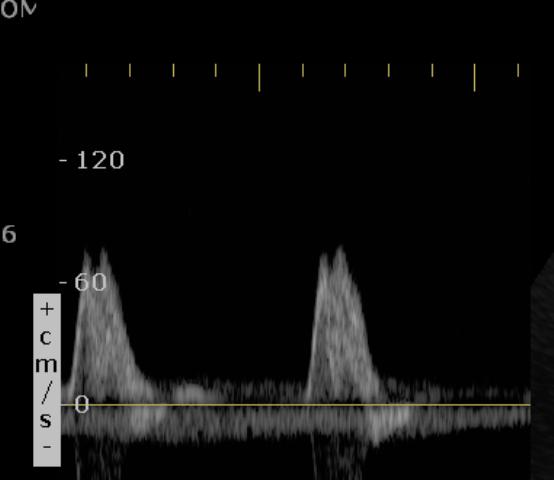

Longitudinal section of abdominal aorta shows a linear echogenic flap in the central of lumen. There are two different shade of  red colour on either side of flap suggests different velocities. It is seen spectral waveform.